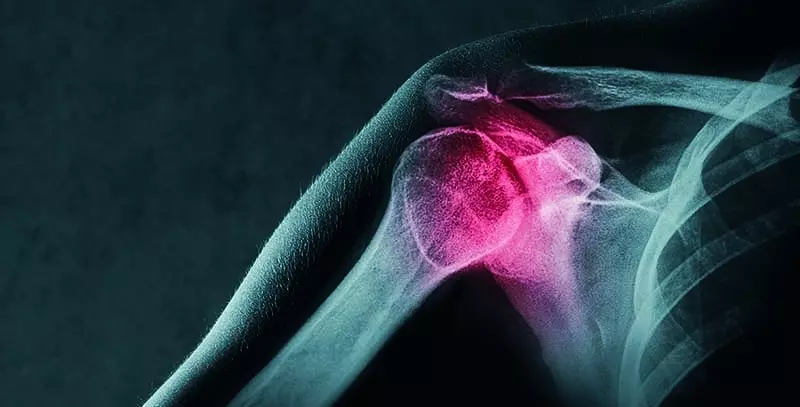

Spośród wszystkich metod obrazowania diagnostycznego narządu ruchu badanie USG wydaje się najbardziej przyjazne dla środowiska fizjoterapeutów. Powodem tego jest jego szeroka dostępność, nieinwazyjność, prostota wykonania, powtarzalność, niskie koszty eksploatacji sprzętu, a przede wszystkim możliwość czynnościowego badania z zastosowaniem testów funkcjonalnych i ortopedycznych z archiwizacją postępów leczenia.

Ilość informacji, jaką otrzymuje wykonujący to badanie, znacząco zależy od zakresu ruchu stawu i możliwości współpracy z pacjentem podczas badania czynnościowego. W tym kontekście w przypadku stawu barkowego warunki do badania są szczególnie sprzyjające.

Ultrasonografia stawu barkowego może być wykorzystywana w warstwie diagnostycznej oraz w warstwie terapeutycznej, gdzie obrazowanie stawu służy jako punkt odniesienia w konstruowaniu pozycji do terapii i autoterapii na zasadzie sprzężenia zwrotnego (sonofeedback – SFB). Do badania używana jest przede wszystkim sonda liniowa w zakresie częstotliwości 7–12 MHz. W wyjątkowych sytuacjach (pacjent o dużych rozmiarach, głęboko położone struktury) może zachodzić konieczność użycia sondy sektorowej (convex) pracującej w zakresie częstotliwości 3–5 MHz.